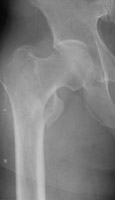

- Click on the image for a larger versionDAP radiograph of the right hip. A third example of an intertrochanteric fracture.